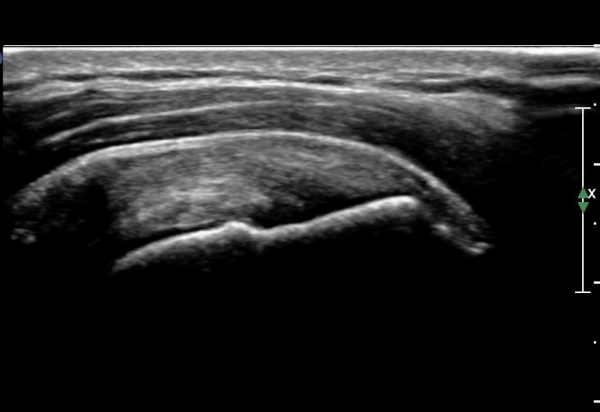

°ßºÀÈ¸Ãø Ãæµ¹ÁõÈıº°Ë»ç(°íÂû »çÁø Âü°í)¿¡¼­ °ßºÀ¿ÜÃø¿¡ ¼ö¾×ÀÌ Àú·ùµÇ°í °Ë»ç ½Ã

°ßºÀ ¾Æ·¡¿¡¼­ ÀâÀ½(crepitus)ÀÌ ´À²¸Áü.(»çÁø 6).